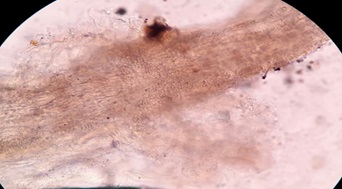

- Nấm da :thấy sợi nấm trong suốt, có vách ngăn, có thể thấy bào tử đốt.

Hình 3: Nấm da